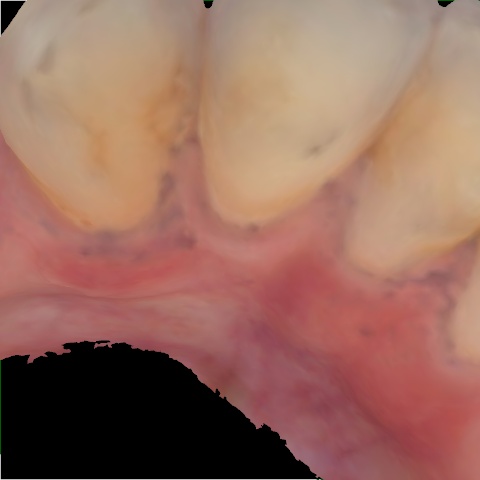

Annotated as "Bad"